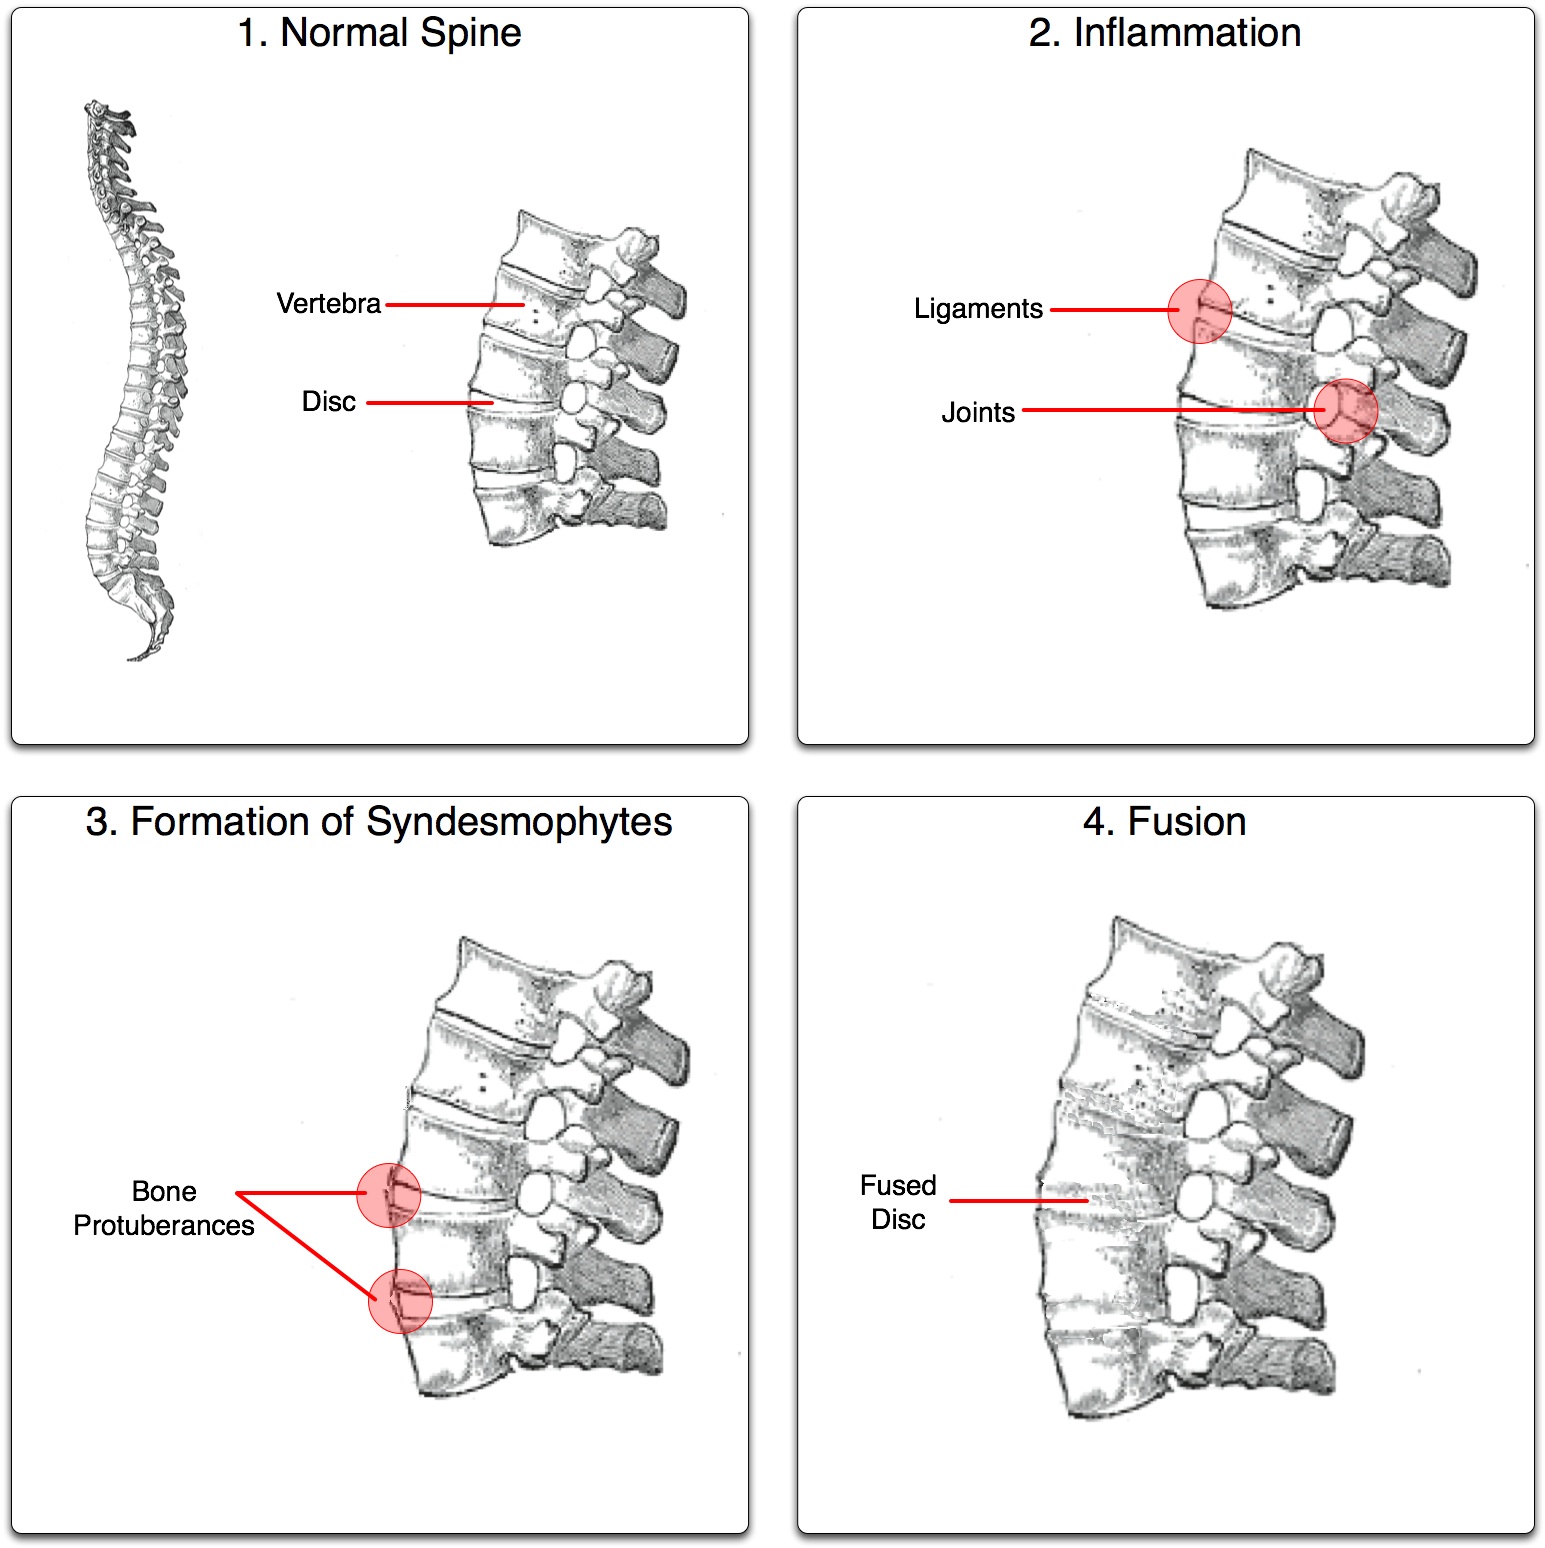

"대나무 척추"는 섬유륜(''anulus fibrosus disci intervertebralis'')의 바깥 섬유가 골화될 때 발생하며, 이는 인접한 척추 사이에 변연 신데스모파이트가 형성되는 결과를 초래한다.

단순 X-ray에서 가장 초기에 나타나는 변화는 천장관절의 침식과 경화이다.[23] 침식이 진행되면 관절 공간이 넓어지고 뼈가 경화된다. X-ray 척추 사진은 신데스모파이트라고 하는 뼈 가시 형성으로 척추가 사각형이 되는 것을 보여줄 수 있으며, 이는 대나무 척추 모양을 유발한다. X-ray 진단의 단점은 강직성 척추염의 징후와 증상이 일반적으로 단순 X-ray에서 확인 가능한 변화가 나타나기 7~10년 전에 이미 나타난다는 것이다. 이는 적절한 치료법을 도입하기 전에 최대 10년의 지연이 발생할 수 있음을 의미한다.[23]

질병이 진행됨에 따라 척추와 요천추 관절이 골화되어 척추가 유합될 수 있다.[44] 이로 인해 척추는 하나의 뼈가 되어 운동 범위가 줄어들 뿐만 아니라 척추 골절의 위험이 높아진다. 척추가 완전히 유합되면 운동 범위가 감소하고 통증이 증가하며, 관절이 완전히 파괴되어 관절 치환술이 필요할 수 있다.[45]

골다공증은 강직성 척추염 환자에게 흔하며, 만성적인 전신 염증과 운동 능력 감소가 원인이다. 장기간에 걸쳐 척추의 골감소증 또는 골다공증이 발생하여 압박 골절과 등의 "혹"을 유발할 수 있다.[46] 척추 후만증은 이동성과 균형 장애를 유발하고, 주변 시야를 손상시켜 낙상 위험을 증가시킨다.[46] 진행된 강직성 척추염의 전형적인 징후는 X-레이에서 신데스모파이트 형성 및 골극과 유사한 비정상적인 뼈 성장이다. 척추 압박 골절에서는 신경 주변 조직 염증으로 인해 감각 이상이 나타나기도 한다.